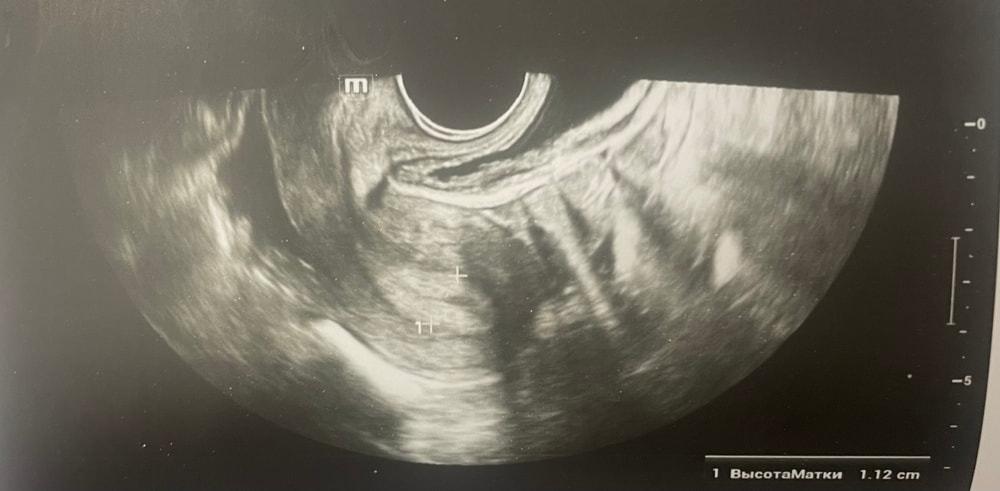

Ждем дня Х/тесты/признаки БДобрый день, мы с мужем планируем беременность и в этом месяце произошло что то странное… дата начала последней менструации 4 октября закончилась 8, овуляцию отслеживала всю неделю почти сначала были бледные еле заметные полоски, 23 октября жирные четкие полоски, 24 октября стала чуть бледнее но яркая, вообщем положительный ещё был, с 25 числа тест уже отрицательный, через день после овуляции 26 числа стала странно себя чувствовать и во время овуляции болел живот то справа то с лева и поясница, так через день после начали болеть соски грудь вообще не болела, живот то болит то нет и с поясницей также, позже появилась небольшая изжога, нога немеет правая не знаю с чем связано), все это началось за 2 недели до месячных в середине цикла скажем так 29 числа пошла на узи спустя 6 дней грубо говоря гиня сказала что у меня была очень хорошая овуляция, что её признаки сохраняются до сих пор так скажем, желтое тело СПРАВО 20 мм, мои симптомы и все это очень похоже на беременность сказали большая вероятность, я очень была рада и надеялась, после узи появились выделения с комочками, до этого были просто густые белые выделения, утром тоже самое, пошла опять к гинекологу она сказала это может быть при ранец беременности сказала какие свечи купить, вечером я попала в не большое ДТП, удар был в поясницу и копчик, живот начал тянуть и поясница сильно болеть, начала болеть сама грудь помимо сосков, живот прошел относительно быстро, а вот поясница ломит до сих пор, решила сходить ещё раз на узи очень испугалась, на узи я пошла 31 через два дня после предыдущего и уже к другому гинекологу, моя на больничном, она сказала, что у меня отсутствуют даже косвенные признаки беременности и желтое тело с ЛЕВО А НЕ С ПРАВО, я не понимаю как такое может быть, очень расстроилась и совсем забыла про фото узи, она мне его не дала только заключение и как выяснилось уже не дадут оно не сохранилось, сказали переделывать, я очень доверяю своему гинекологу, но по заключению второго врача о беременности не может быть и речи в этом цикле, я не понимаю как желтое тело оказалось с лево если оно точно было справа в этом я уверена, а вторая врач уверяет во Братном, живот в обуляцию хоть и болел с двух сторон но больше справа помойму, вообщем я не понимаю есть ли шанс что я беременна или все таки нет, я понимаю что это слишком рано, до задержки ещё 4 дня, но мне плохо уже неделю по симптомам даже больше это же не просто так, я прикреплю фото заключения, могу ли я быть беременна, если посмотреть на эти заключения хотябы, подскажите пожалуйста фото узи относятся к 29.10, без фото 31.10